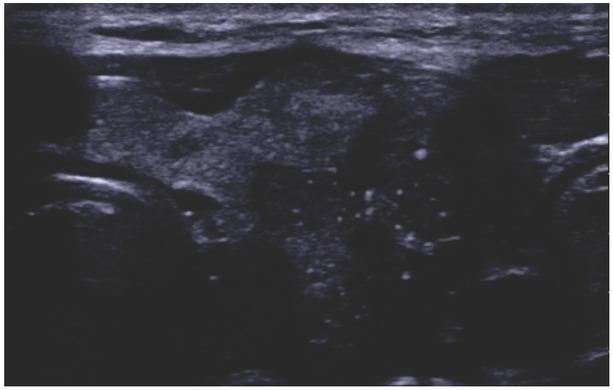

Fig. 2